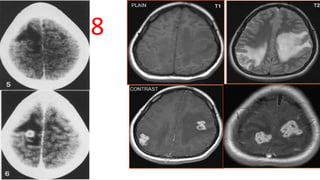

Tuberculoma

• CT- Hypo to hyperdense mass with moderate to marked edema, Iso to

hyperdense basal exudate effaces CSF spaces, fills basal cisterns, sulci

• CECT- "Target sign"

• MRI - Non-caseating : Hyper on T2 and hypo on T1 W

- Caseating : Iso- to hypointense on both T1 and T2 images, with

an iso- to hyperintense rim on T2 W

• CEMR: Nodular or ring-like enhancing lesions- 1 mm to 2 cm.